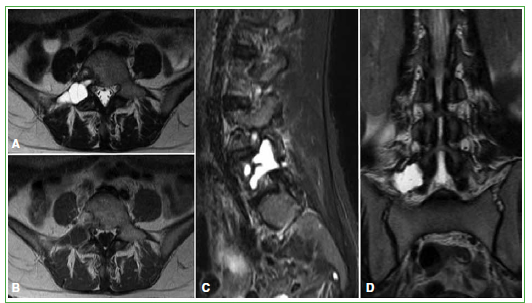

En la RM de columna lumbosacra con contraste endovenoso, se identificó la misma lesión expansiva de 24 mm x 33 mm x 16 mm, de contenido líquido, con tabiques internos y adelgazamiento de la cortical ósea, centrada en el pedículo derecho de L5 y con extensión al cuerpo vertebral, faceta y apófisis transversa derecha (Figura 2).

Figura 2.

Resonancia magnética. A. T2, corte axial. B. T1, corte axial. C. STIR, corte sagital. D. T2, corte coronal. Lesión de intensidad de señal líquida (hiperintensa en secuencia T2 y STIR e hipointensa en secuencia T1) con tabiques internos, expansiva que genera adelgazamiento de la cortical ósea, centrada en el pedículo derecho de L5 y con extensión al cuerpo vertebral, faceta y apófisis transversa derecha.